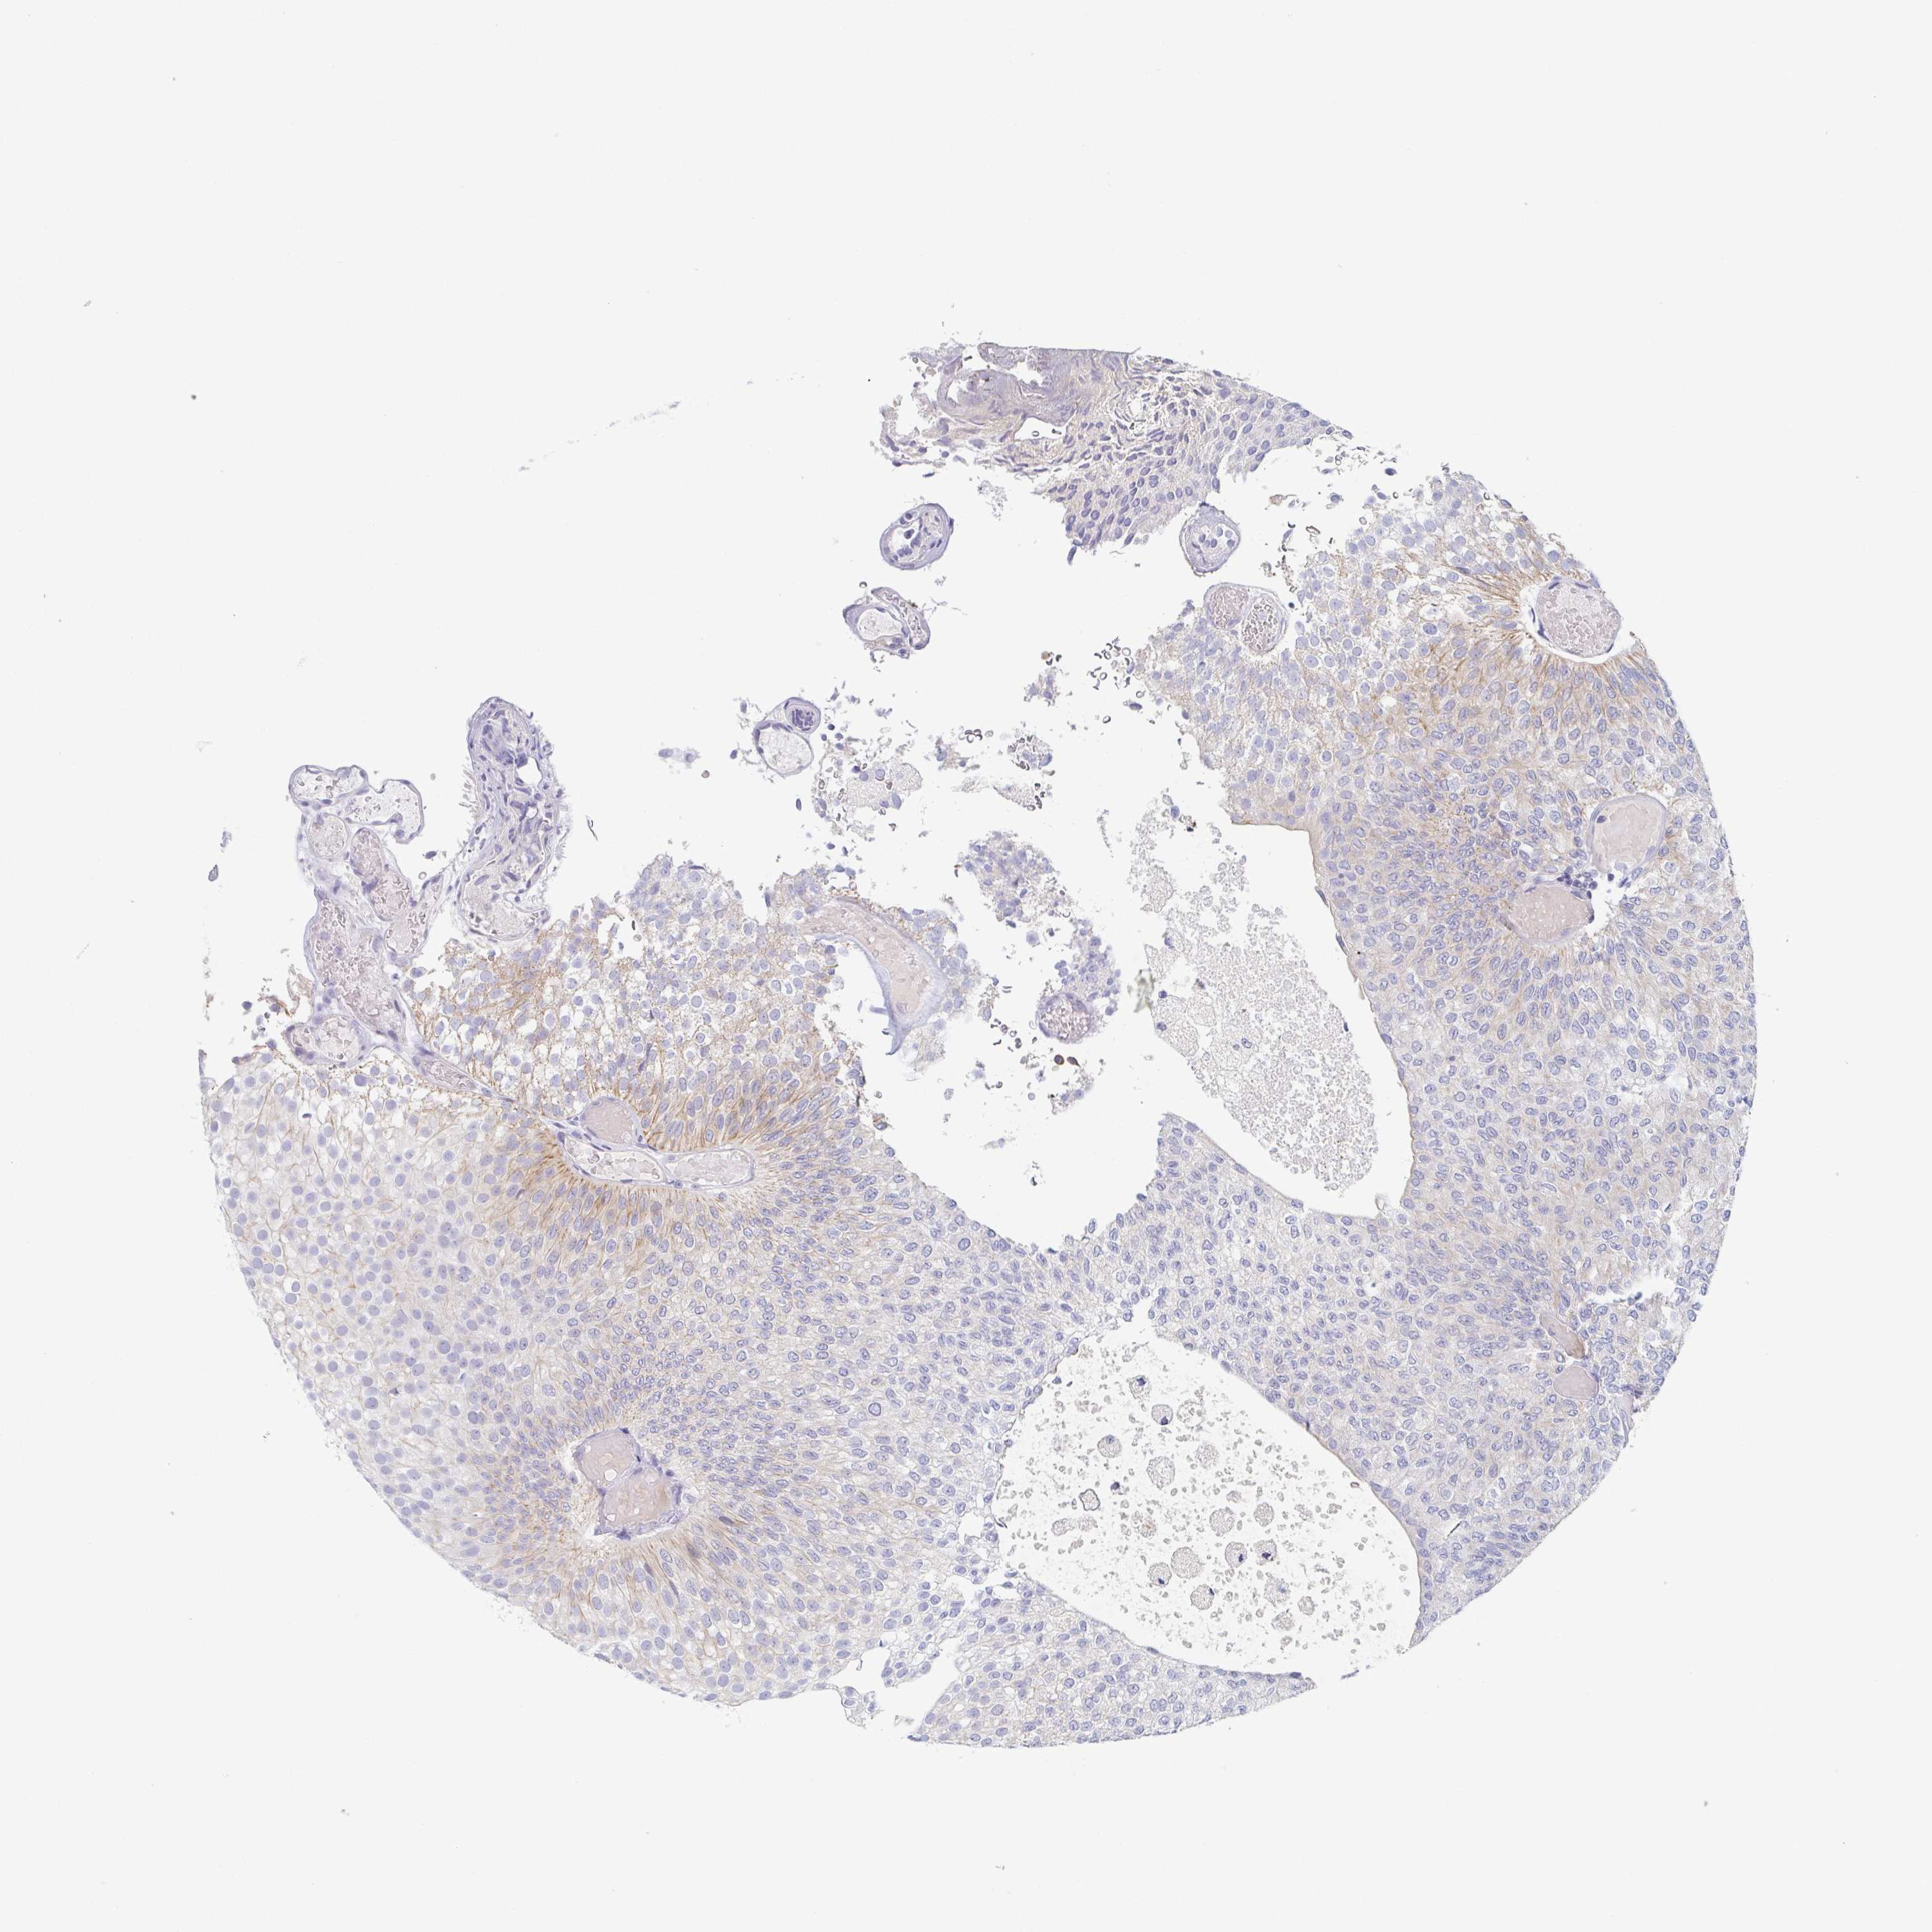

UROTHELIAL CANCER - Protein expressioni

A mouse-over function shows sample information and annotation data. Click on an image to view it in a full screen mode. Samples can be filtered based on level of antibody staining by selecting one or several of the following categories: high, medium, low and not detected. The assay and annotation is described here.

Note that samples used for immunohistochemistry by the Human Protein Atlas do not correspond to samples in the TCGA dataset.

Antibody stainingi

Antibody staining in the annotated cell types in the current human tissue is reported as not detected, low, medium, or high, based on conventional immunohistochemistry profiling in selected tissues. This score is based on the combination of the staining intensity and fraction of stained cells.

Each image is clickable and will lead to virtual microscopy that enables deeper exploration of all samples and also displays staining intensity scores, fraction scores and subcellular localization as well as patient and tissue information for each sample.

Antibody HPA053343

Staining

High

Medium

Low

Not detected

Intensity

Strong

Moderate

Weak

Negative

Quantity

>75%

75%-25%

<25%

None

Location

Nuclear

Cytoplasmic/membranous

Cytoplasmic/membranous,nuclear

Urothelial carcinoma, High grade

Urothelial carcinoma, Low grade